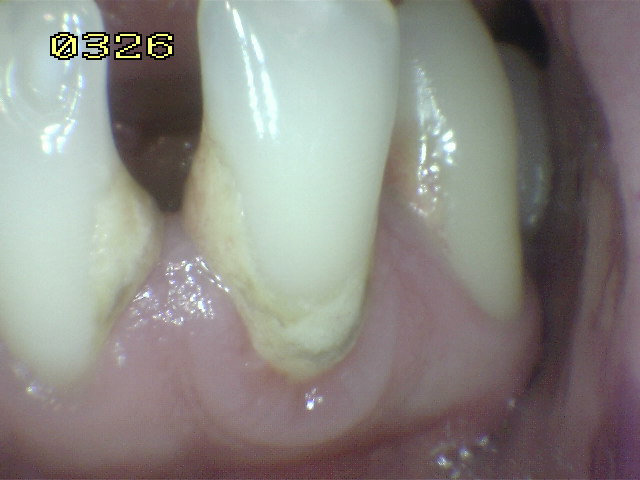

Código 0:

La

superficie de la raíz

no presenta ninguna

coloración

inusual

que lo distingue de

los alrededores o

las áreas adyacentes

de la raíz,

ni

exhibir un

defecto de la superficie,

ya sea en

la unión cemento-esmalte

o totalmente en

superficie de la raíz.

tiene un contorno

anatómico

natural. Ver imagen inferior.

pueden mostrar

una pérdida definida

de

la continuidad de

la superficie

o el contorno

anatómico que no

es

consistente con el

proceso de caries

dental.

Esta pérdida de

integridad de la superficie

por lo general

se asocia con la dieta

(erosión)

o hábitos

(abrasión).

Estas condiciones

ocurren generalmente en la

cara vestibular.

Estas

zonas

suelen ser

lisa, brillante y

dura.

La abrasión

se caracteriza por un

claro contorno definido,

con un borde

afilado,

mientras que

la erosión

tiene una frontera

más difusa.

Ninguna de estas condiciones

muestra

decoloración.